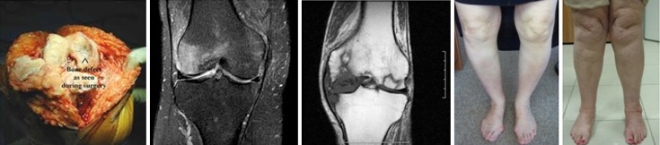

Οι διάφορες φάσεις της αρθρίτιδας έχουν διαφορετική απεικόνιση στην ακτινογραφία και στην μαγνητική τομογραφία. Στην ακτινογραφία διακρίνεται η λέπτυνση του χόνδρου, η παραμόρφωση του άξονα, η σκλήρυνση του οστού και τα οστεόφυτα.

Στη μαγνητική τομογραφία εμφαίνονται οι βλάβες στους μηνίσκους (ρήξη ή εκφύλιση) των χιαστών συνδέσμων η ελάττωση του πάχους του χόνδρου, η νέκρωση του χόνδρου και η νέκρωση των υποκειμένων οστών.